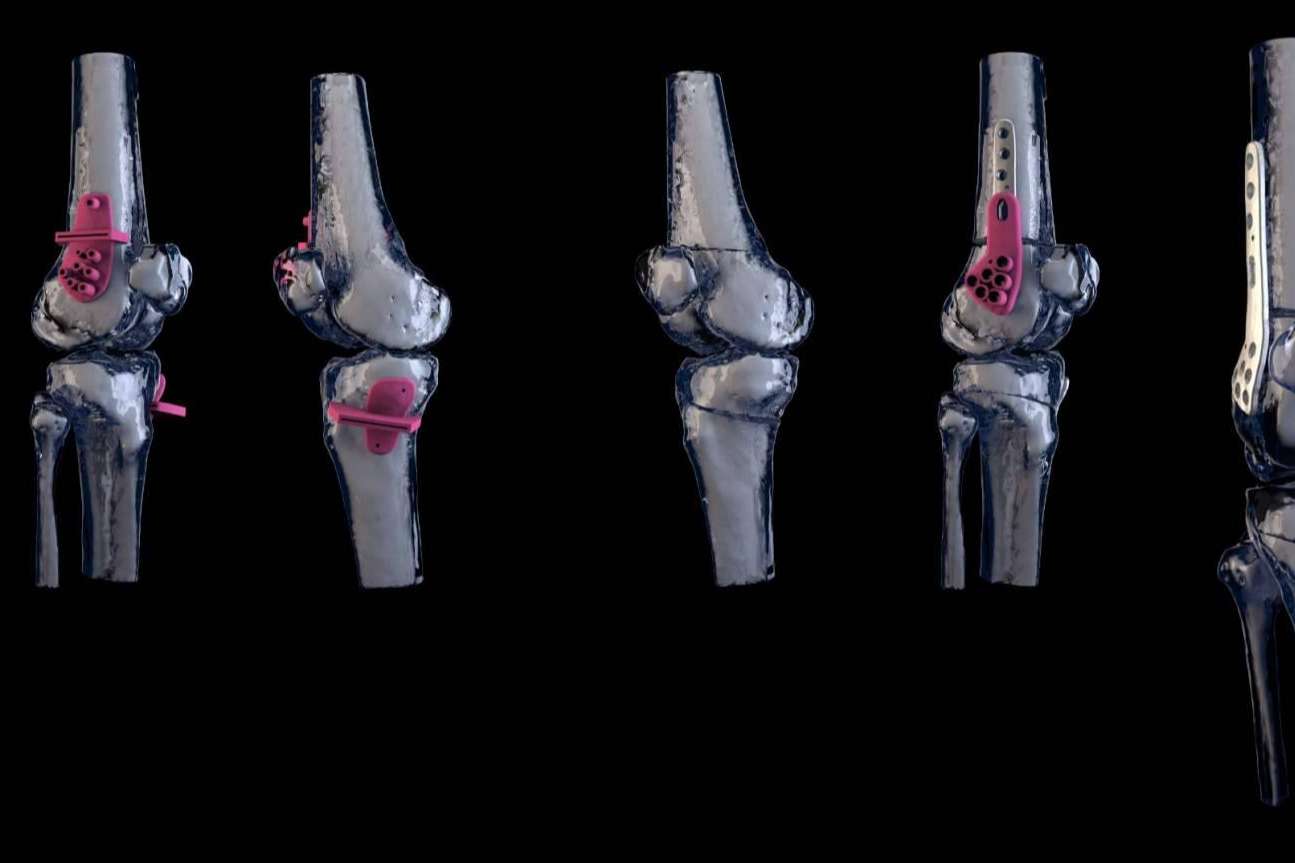

Es en este campo que nace KOOBO®, una empresa joven que cuenta en su equipo con expertos bioingenieros en el manejo de últimas tecnologías y que apuesta por el desarrollo de implantes, guías quirúrgicas y biomodelos personalizados para mejorar la calidad de vida de los pacientes, cubriendo todas las fases: desde el diseño hasta su fabricación.

Las piezas personalizadas se fabrican, utilizando las últimas tecnologías de fabricación aditiva, mecanizado de alta precisión y herramientas CAD.

Por un lado, los biomodelos personalizados permiten una planificación pre-quirúrgica más exacta. Por otro lado, se minimizan los tiempos de espera para la recepción de las piezas y el tiempo del abordaje quirúrgico, ya que no es necesario llevar a cabo una adaptación de los implantes. Consecuentemente, se reduce el riesgo de infecciones nosocomiales y se facilita el proceso de recuperación del paciente.